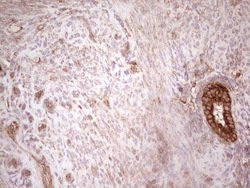

- Experimental details

- Immunohistochemical staining of paraffin-embedded Adenocarcinoma of Human breast tissue using anti-WIBG mouse monoclonal antibody. (Heat-induced epitope retrieval by 1 mM EDTA in 10mM Tris, pH8.5, 120C for 3min, TA806496)

- Validation comment

- IHC